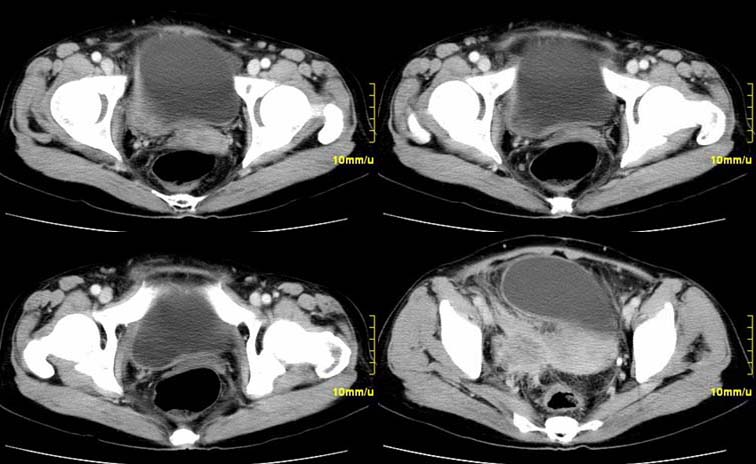

患者,52,右下腹疼痛一月,当时有发热,抗炎治疗20余天,至今仍疼痛,且有低热。

增强

右附件区软组织包块,内囊变坏死,边缘模糊,与子宫,与膀胱分界不清,增强强化与子宫密度相近.盆腔内无肿大淋巴结考虑炎性包块可能性大。

右附件区软组织包块,内可见坏死,边界不清,周围软组织及脂肪组织可见密度增高,膀胱右侧壁增厚,并且呈膨胀不全的改变,考虑炎性包裹,不知道有没有手术史??

临床特点:

右下腹疼痛一月,当时有发热,抗炎治疗20余天,至今仍疼痛,且有低热,具有典型炎症的临床表现。

ct表现:

右侧附件见一肿块,边缘与周围组织分界不清,增强扫描见肿块明显强化,越到后期强化越明显,中央见坏死,内壁光整,与临近子宫壁、直肠及膀胱后壁均见炎症波及。这种厚壁肿块、内缘光整外缘模糊、增强扫描强化越后越强是附件脓肿典型的ct表现。

诊断:

右侧卵巢输卵管慢性脓肿,炎症波及临近子宫、直肠及膀胱形成粘连。